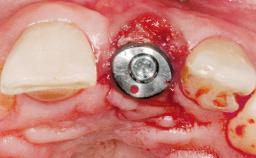

Immediate Placement of an Implant in a Maxillary Right Central Incisor Site

A 30-year-old female patient was referred to the office for the treatment of tooth 11. Her chief concern at the initial visit was to inquire, “Why is my tooth pink?” Upon clinical examination, it was determined that tooth 11 had a previous history of trauma and that the clinical crown had become noticeably pink in color as a result of internal resorption. This diagnosis was confirmed radiographically, indicating a large radiolucency involving the central and distal portions of the clinical crown. It was determined that restoration of this tooth was not possible, and that extraction was indicated. The presence of a mid-line diastema, which the patient wanted to reproduce, directed the treatment plan for tooth replacement utilizing a dental implant.

Bone Augmentation Horizontal|Simultaneous

Augmentation Materials Autogenous chips|Membrane

Placement Protocol Immediate implant placement

Socket Integrity Sufficient, with intact bone walls

Bone Volume Sufficient, with intact walls